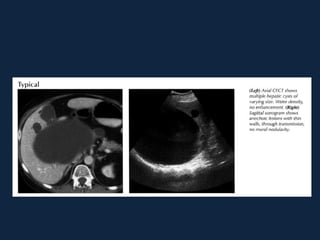

Cistos Simples

► Lesões comuns (5-14% população)

► Solitários (mais frequente) ou múltiplos (mais que 10, doença

policística deve ser considerada)

► Originam-se do epitélio do ducto biliar, sendo revestidos por

camada única de epitélio cúbico

► ♀s (5:1)

► Assintomáticos

► Complicações: infecção ou sangramento

►Contornos bem definidos

►Atenuação baixa (semelhante a água, <20 UH)

►Sem realce ao meio de contraste

►Pode haver calcificação na parede do cisto

►Não há septações ou nodularidade mural